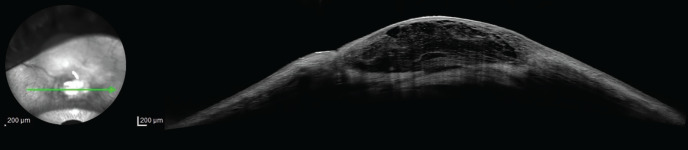

小梁切除术是用于降低青光眼患者眼压(IOP)的主要手术方法。尽管效果显著,但也可能导致严重的并发症,包括眼压过低、脉络膜渗出、睑板腺炎和睑板腺渗漏。眼泡渗漏需要及时的药物或手术干预,以防止出现严重的并发症,如眼泡炎和眼泡相关性眼内炎。近年来,胶原交联术(CCL)的适应症已从角膜异位疾病扩展到角膜炎和眼泡渗漏等各种眼部疾病。在此,我们介绍一例 70 岁男性患者的病例,他患有血管囊性眼泡渗漏。患者在接受结膜 CCL、局部庆大霉素、多佐胺/噻吗洛尔复方制剂和治疗性隐形眼镜的综合治疗后,眼泡渗漏停止,眼压上升。

Trabeculectomy is a primary surgical procedure used to reduce intraocular pressure (IOP) in patients with glaucoma. Despite its effectiveness, it can lead to significant complications, including hypotony, choroidal effusion, blebitis, and bleb leaks. Bleb leaks require prompt medical or surgical intervention to prevent severe complications such as blebitis and bleb-associated endophthalmitis. In recent years, the indications for collagen cross-linking (CCL) have expanded beyond corneal ectatic diseases to include various ocular conditions such as keratitis and leaking blebs. Here, we present the case of a 70-year-old male patient with a leaking avascular cystic bleb. Following treatment with a combination of conjunctival CCL, topical gentamicin, a dorzolamide/timolol combination, and a therapeutic contact lens, the patient experienced cessation of bleb leakage and an increase in IOP.